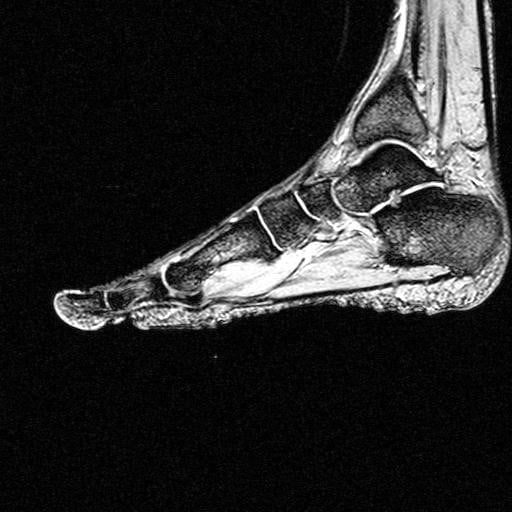

Rezonans magnetyczny stopy

Rezonans magnetyczny stopy – możliwości diagnostyczne

Dzięki niezwykle dokładnemu badaniu obrazowemu, jakim jest rezonans magnetyczny stopy, można dokonać oceny głęboko położonych więzadeł, a także uwidocznić przyczyny ucisku nerwów, odpowiedzialne za uczucie drętwienia i pieczenia w obrębie stopy. Rezonans magnetyczny stopy może być pomocny również w diagnozowaniu neuropatii uciskowej nerwów podeszwowych, jaką jest tzw. nerwiak Mortona, w przypadku której zwykłe badanie USG często nie jest wystarczająco dokładne. Badanie to często wykorzystywane jest również do oceny ciągłości ścięgien, które w obrębie stopy często narażone są na drobne, trudne do zdiagnozowania naderwania, a także stanów zapalnych m.in. rozcięgna podeszwowego.

Rezonans magnetyczny stopy do obrazowania struktur wewnątrz naszego ciała wykorzystuje właściwości pola magnetycznego i jego wpływ na atomy w naszym organizmie. Magnes stanowiący rdzeń rezonansu wysyła w głąb naszego organizmu impulsy, które pobudzają cząsteczki naszych tkanek. Wytwarzany przez nie sygnał jest rejestrowany przez cewki odbiorcze, a następnie przetwarzany przez specjalne oprogramowanie na widoczny na ekranie obraz.

Jedną z głównych zalet jaką posiada rezonans magnetyczny stopy jest możliwość wykonywania przekrojów w różnych płaszczyznach: pionowej, poziomej oraz skośnych, co zwiększa możliwości diagnostyczne.